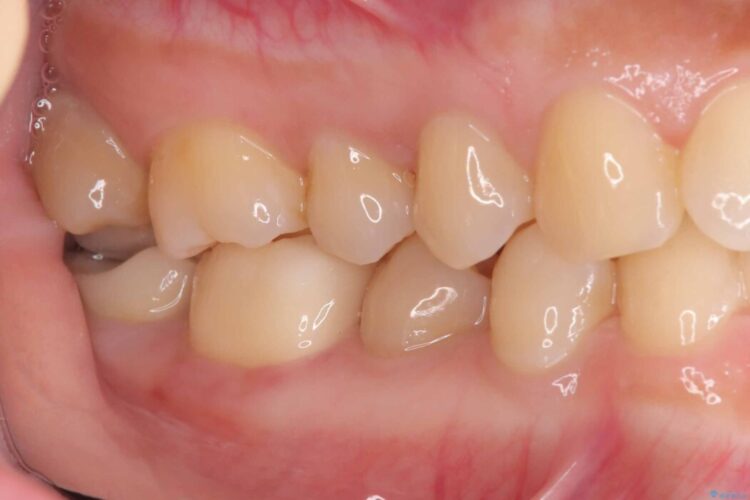

治療後について

クラウンにすることで、歯全体を保護しながら、見た目も自然で長期的に安定した状態を維持しやすくなります。

「できるだけ歯を削りたくない」という考えも大切ですが、状態によっては、長持ちさせるためにあえて全体を覆う治療が適している場合もあります。